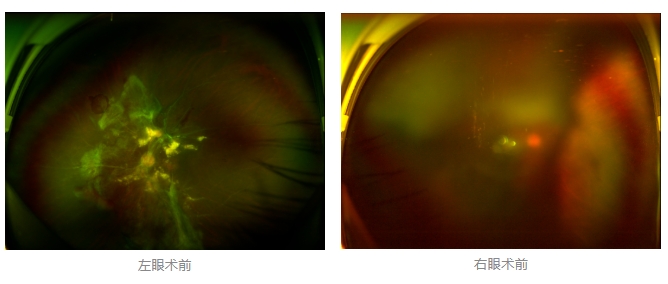

經(jīng)廈門眼科中心眼底病專科行政主任王曉波檢查后,確診其雙眼糖尿病視網(wǎng)膜病變VI期,伴發(fā)雙眼視網(wǎng)膜脫離和黃斑水腫,且右眼視網(wǎng)膜上增殖膜叢生,若再不盡快進行治療,恐有失明風(fēng)險。

面對陳先生的復(fù)雜病情,王曉波主任采用玻璃體切割術(shù)聯(lián)合膜切除術(shù)等方式,精細剝離牽拉視網(wǎng)膜的增殖膜,復(fù)位脫離的視網(wǎng)膜,同時進行玻璃體腔注藥促進黃斑水腫吸收。